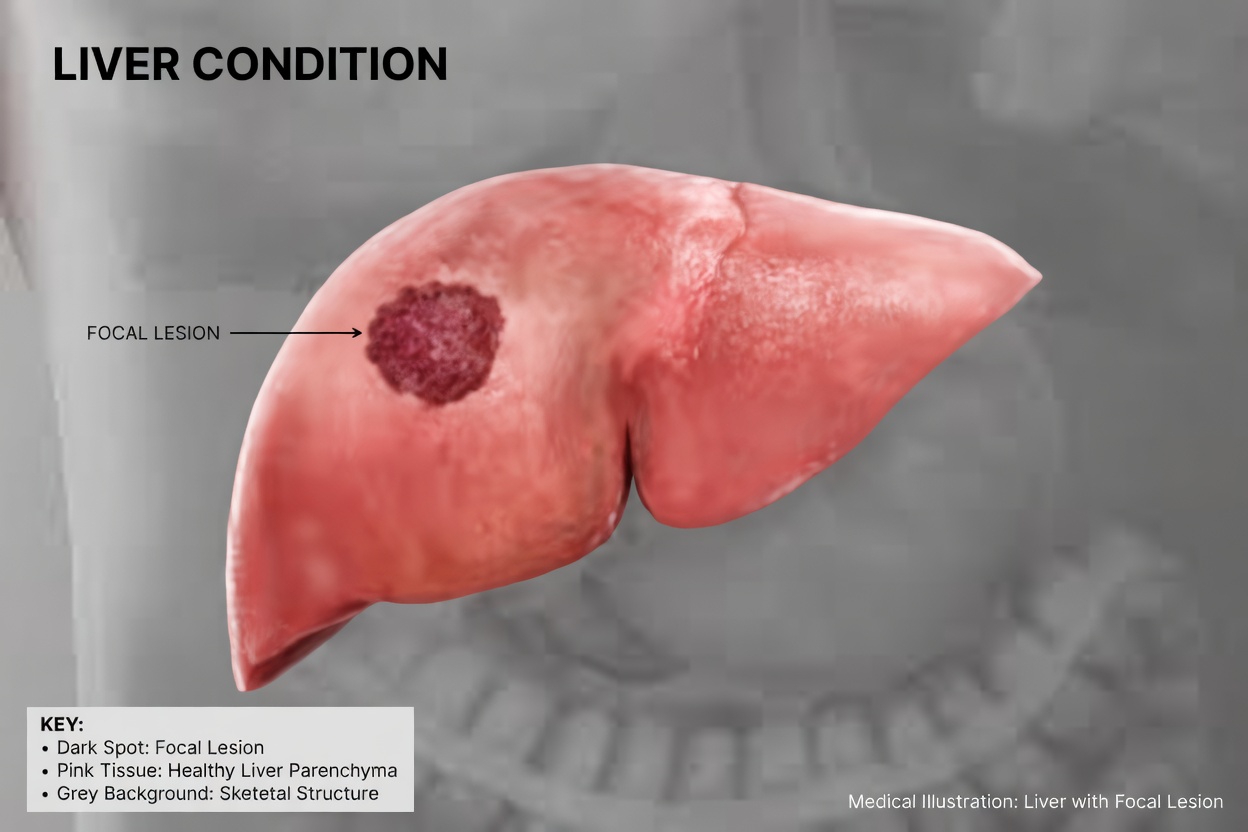

But these small changes may be your body’s way of signaling that your liver is not working as well as it should. Because the liver helps filter toxins, process nutrients, and support digestion, problems can develop quietly at first. Many liver conditions cause little or no pain early on, which is why unusual symptoms often go unnoticed.

Conditions such as non-alcoholic fatty liver disease affect millions of people and frequently progress without dramatic early symptoms. The lack of severe pain can create a false sense of security, causing people to ignore symptoms until they become more obvious.

7. Yellowing of the Skin or Eyes

Anna, 59, noticed a faint yellow tint in the whites of her eyes. It was subtle, but enough to make her concerned.

This yellowing, known as jaundice, happens when bilirubin builds up in the body. It is one of the more familiar signs of liver trouble, but mild cases can still be overlooked, especially in the early stages.